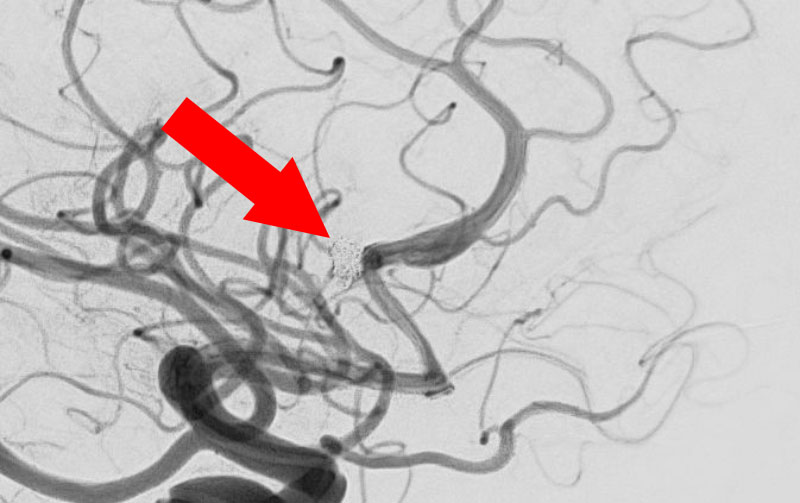

No.1627 手術前

No.1627 手術中

No.1627 手術後